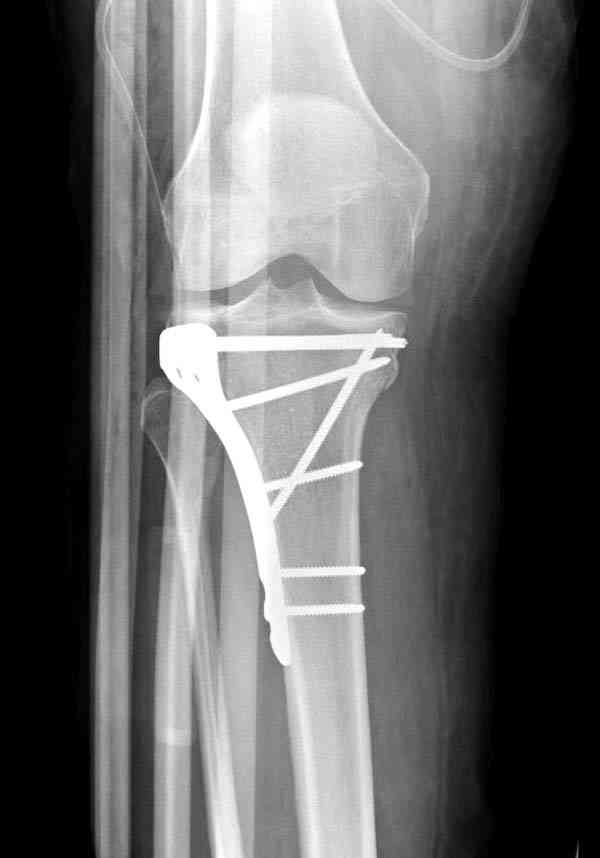

Это техника применяется, когда имеется

центральная импрессия, а при ипрессии с краевым переломом - после приподнимания импрессии опорная (Butress) пластина, как на снимке.